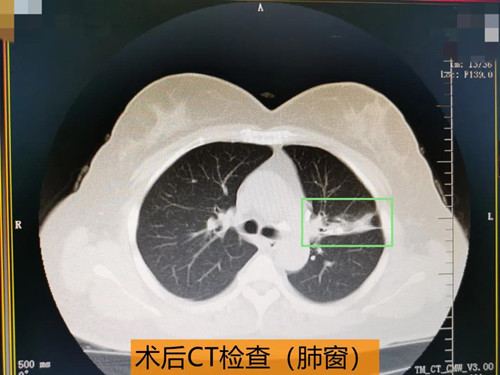

起初王女士对支气管镜检查有些抵触、担忧,为了消除王女士的焦虑、恐惧情绪,张主任详细讲解了支气管镜检查对于疾病诊治的必要性,并建议王女士可以选择无痛支气管镜检查以减少检查过程中的不适。消除了顾虑的王女士来到呼吸内科接受了支气管镜检查,支气管镜下的影像也让医生们大吃一惊,原来阻塞王女士左肺上叶支气管的不是肿瘤,也不是痰栓,而是像被腐蚀的牙齿一样坚硬的异物,术前了解到王女士并没有异物吸入史,看来这块异物应该是生长在支气管里的,张主任在仔细探查及判断异物形态及与周围组织的关系后,果断决定在进行气管镜检查的同时,将该异物通过气管镜取出,并行病理检查,果然取出的异物病理提示是钙盐沉积,也就是说这是一颗长在支气管里的结石。取出支气管结石后,王女士呼吸顺畅,可自主咳痰,心慌、气短症状明显改善,经抗感染治疗后,胸痛症状缓解。之前的症状都是这块结石惹的祸,病因查明,问题解决,结石取出,困扰王女士许久的心里“石头”终于落地了。